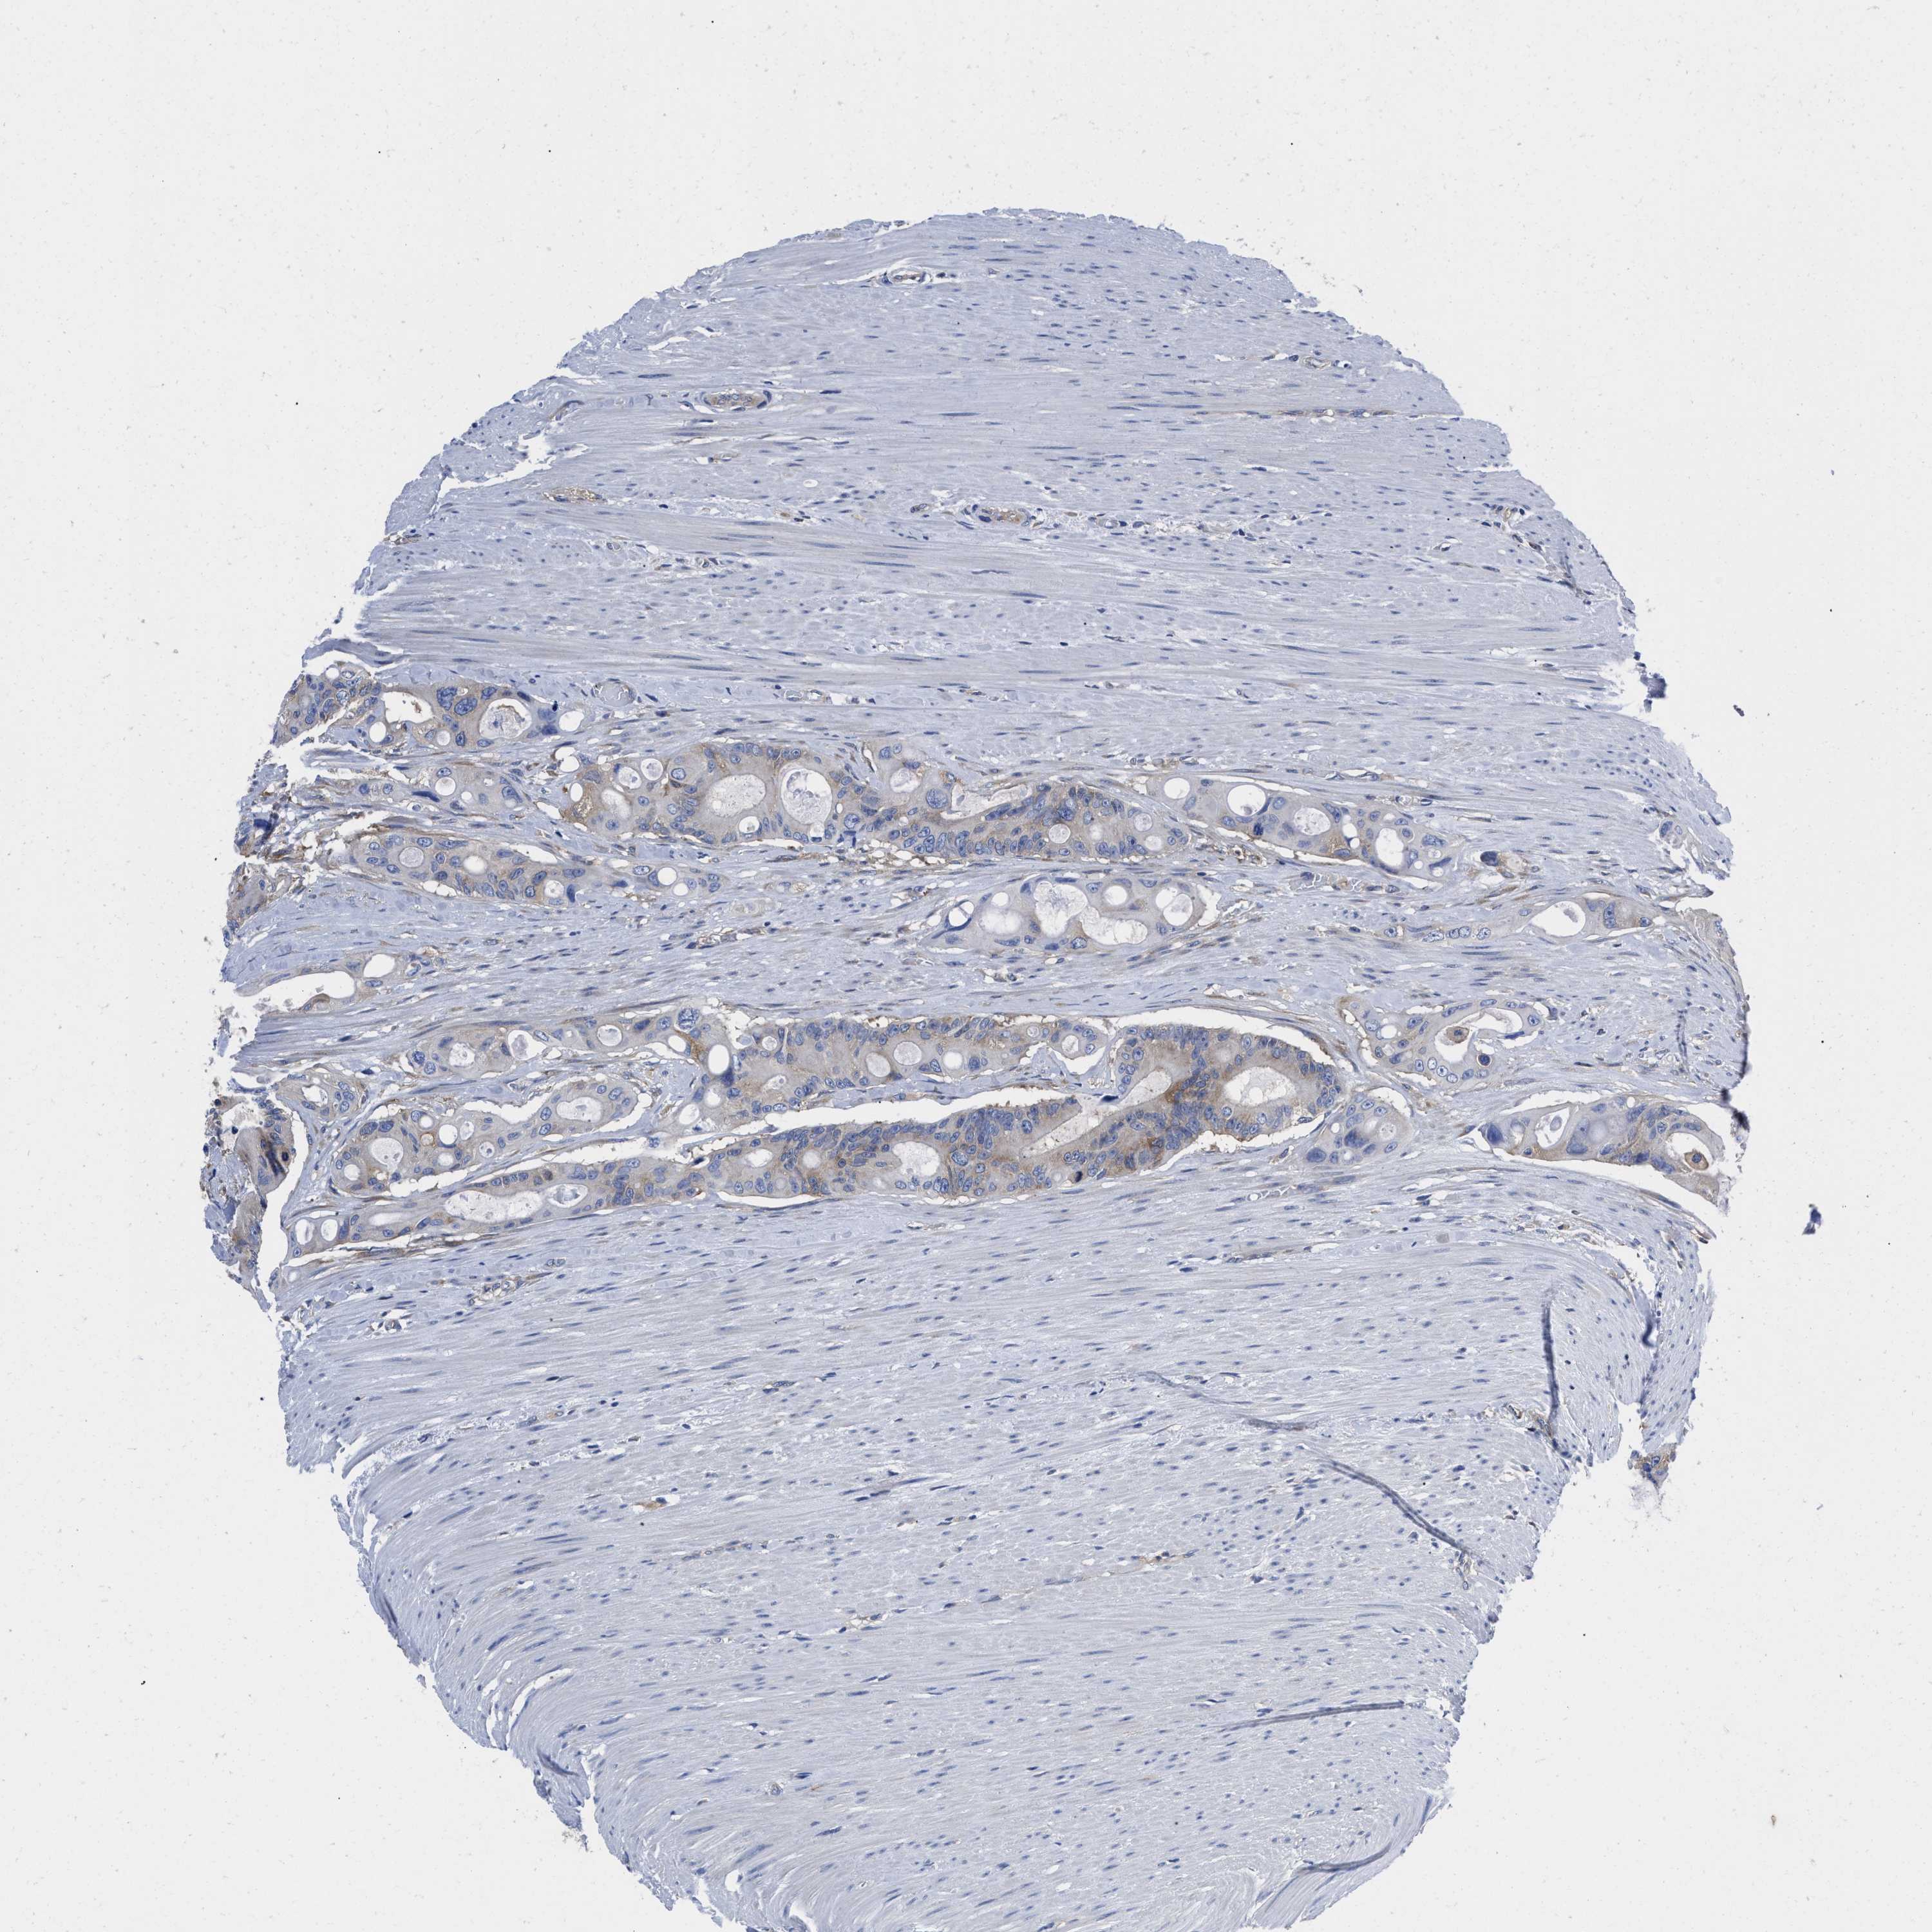

CANCER COLORECTAL CANCER Show tissue menu

COAD TCGA COAD VALIDATION READ TCGA READ VALIDATION PROTEIN COAD CPTAC PROTEIN EXPRESSION

ANTIBODIES

AND

VALIDATION